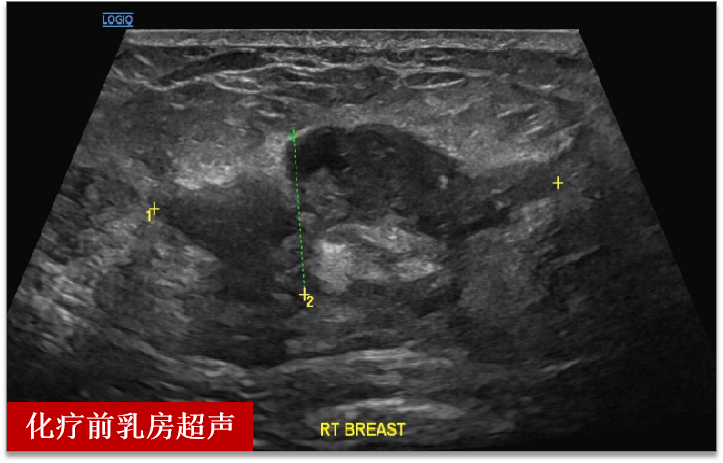

王女士(化名),半年前发现右乳肿物

没有引起重视,近来发现肿块明显增大

来到昆山市一医院乳腺科门诊就诊

检查后发现肝部多发占位

经过穿刺后病理确诊乳腺癌伴肝脏转移

两个周期的化疗后

超声检查提示肝脏肿瘤完全消失

乳房肿瘤较前缩小